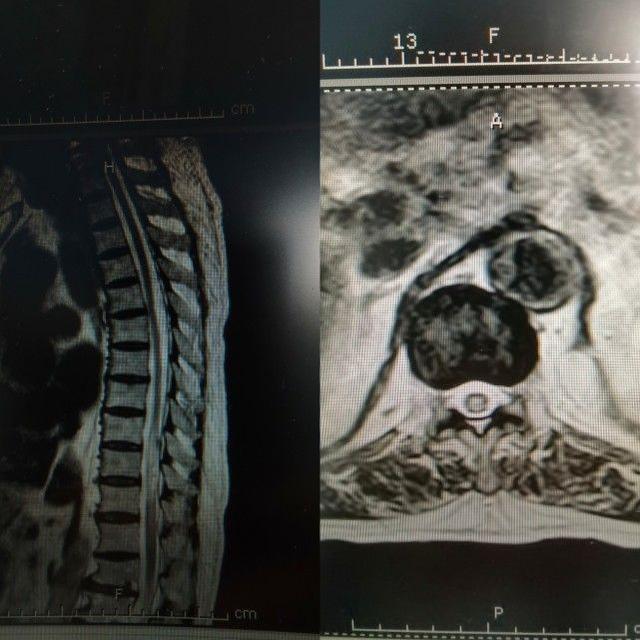

脊髓血管畸形

43岁的杨先生,2个月前出现双下肢麻木等症状,入院前一天症状加重。医院完善相关检查后最终诊断为脊髓血管畸形。给予减轻水肿、改善循环、营养神经、缓解神经痛等对症治疗,肢体症状改善较弱,目前需进一步脊髓血管造影检查。